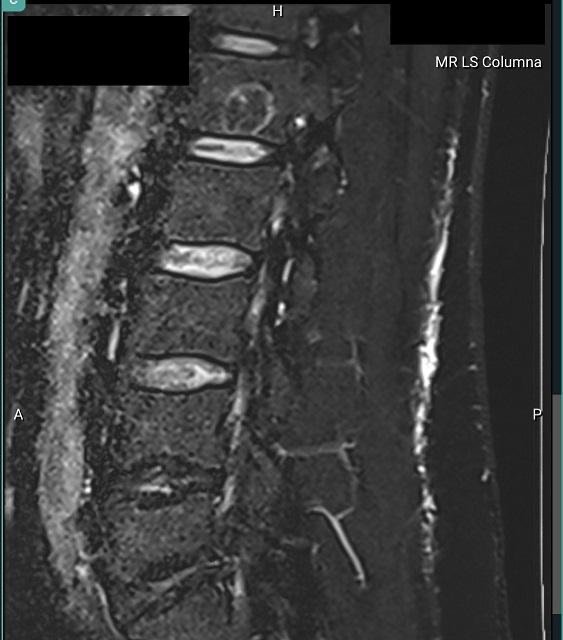

Gjest 5780d...00a Skrevet 15. oktober 2023 Skrevet 15. oktober 2023 Dette er forresten hva jeg stusser over Den runde dingsen på ryggsøylen Anonymous poster hash: 5780d...00a